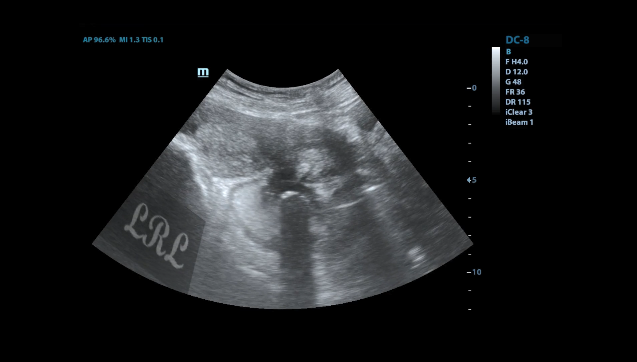

治疗7周后(2022-03-01日)超声示:

直肠壁仅可见一大小约2.1x1.0cm小低回声结节,其余结节及溃疡均已不显示。